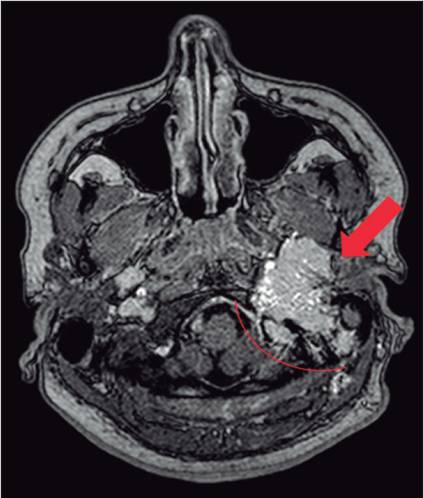

Femenina de 31 años, en control desde 2013 en Otorrinolaringología (ORL) del Hospital Calderón Guardia, por historia de inicio de hipoacusia izquierda progresiva posterior a trauma timpánico dos años previos, que posteriormente asoció tinnitus pulsátil izquierdo, disfonía y disfagia lógica. Al llegar al servicio de ORL, se realiza otoscopía, la cual evidencia una lesión pulsátil violácea que llena todo el conducto auditivo externo izquierdo distalmente, sin otorrea. Se efectúa tomografía axial computada en octubre de 2013, donde se describe que impresiona erosión del tegmento timpánico y masa que llena oído medio y parte del oído externo. Resonancia magnética nuclear (RMN) demuestra un proceso infiltrativo tumoral, localizado en la fosa yugular izquierda que abarcaba el hipotímpano, proyectándose en el conducto auditivo externo del lado izquierdo, inferiormente extendido al espacio carotídeo izquierdo y en el área superior infiltrando la duramadre, que recubría el seno sigmoideo y el seno transverso del lado izquierdo, con un componente de tejidos blandos retromastoideo izquierdo; la lesión refuerza tras la administración de contraste y presenta muchos pedículos vasculares intratumorales, y produce ligero efecto de masa, dado por la compresión del parénquima cerebeloso adyacente.

Posterior a la RMN se establece una impresión diagnóstica de meningioma versus paraganglioma (Figura 1). En noviembre de 2013 se lleva paciente a hemodinamia por el Servicio de Neurocirugía para embolización neuroendovascular con onyx de glomus yugulotimpánico Fisch D2 (Cuadro 1), y de nuevo se realiza embolización residual una semana después con onyx, donde se encontró persistencia de ramas maxilar interna y occipitales. En dicha ocasión se logra embolizar el 100 % del aporte arterial. La paciente fue egresada en ese momento en buenas condiciones, persistiendo con hipoacusia, y ameritó gastrostomía endoscópica percutánea y uso de sonda para alimentación durante 5 meses, por persistencia de disfagia; por lo demás, con sus capacidades conservadas. En 2015 se realizó una segunda embolización neuroendovascular de la lesión, por nuevo crecimiento, y en 2017, durante la cita de control, la paciente refiere cuello abotagado y cambios en el tono de la voz, por lo que se repite la RMN, que demostró persistencia de glomus yugulotimpánico. En esta ocasión se desarrolla sesión multidisciplinaria con ORL y neurocirugía para valorar posibilidad de resección de lesión con Gamma knife, lo cual se solicitó a 2 hospitales extranjeros (Miami y Colombia), y ambos rechazaron el caso por el tamaño de la masa.